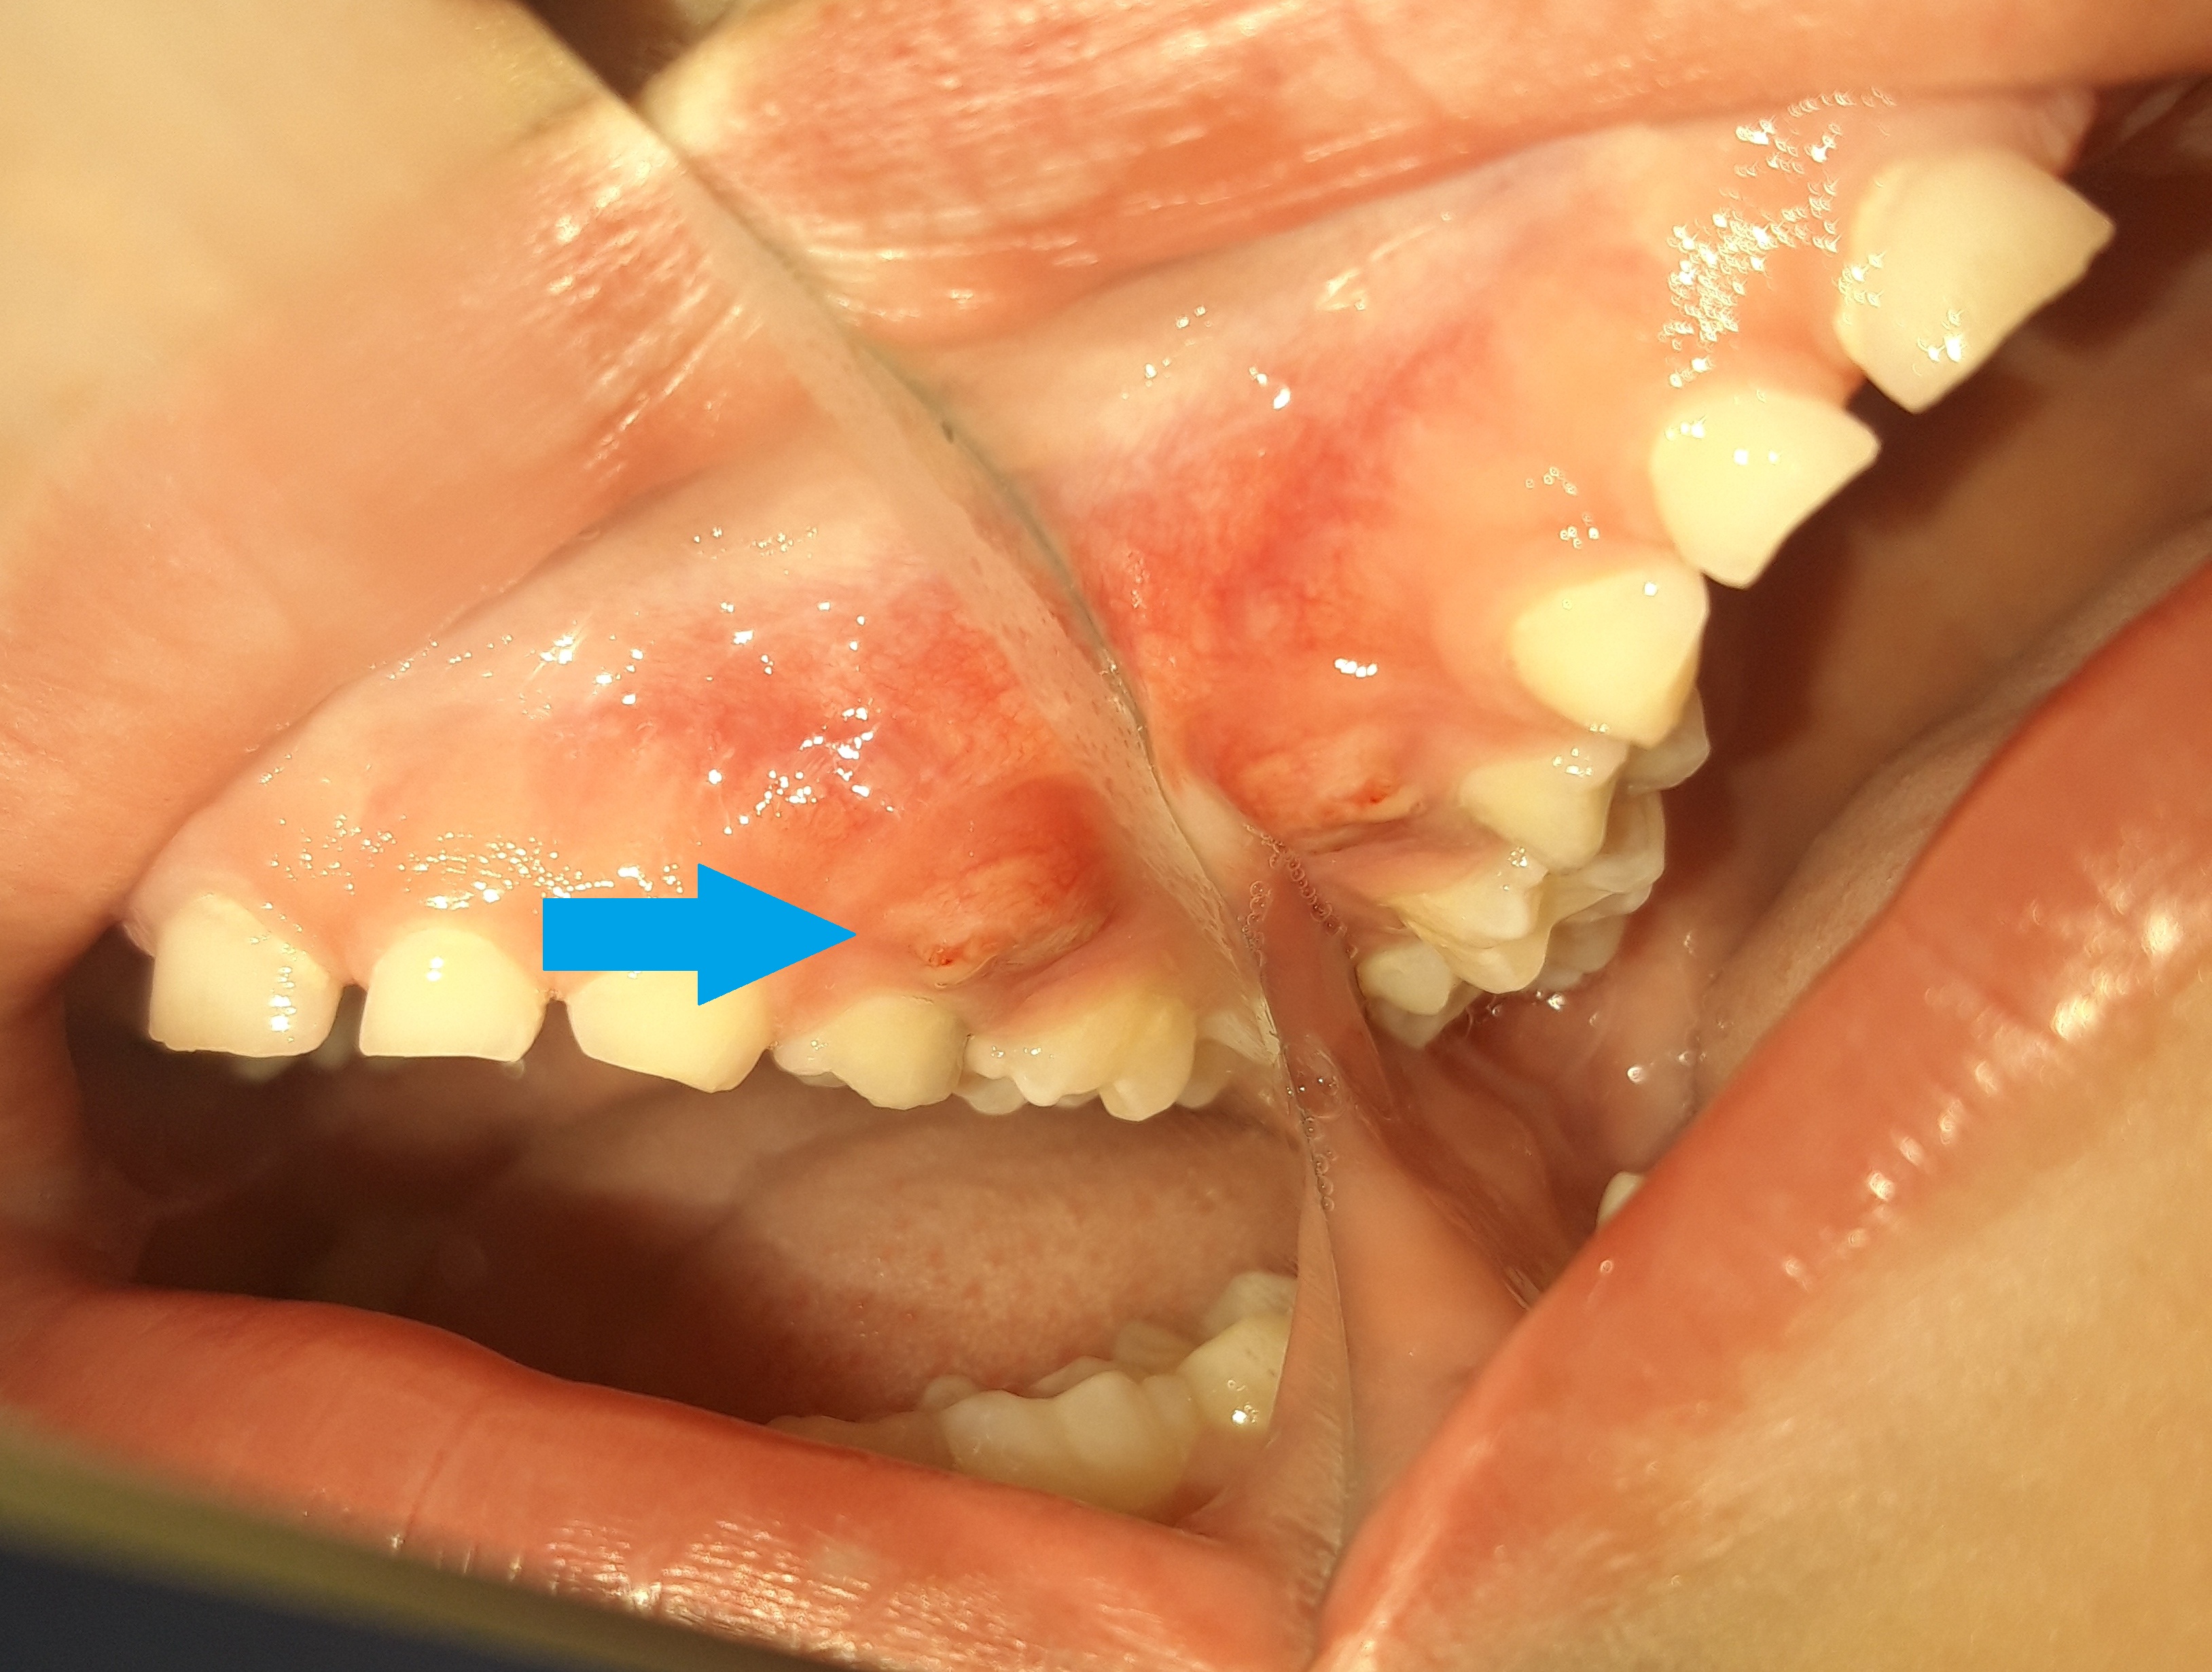

Περιστατικό – Συρίγγιο σε παιδικό δόντι

Ο μικρός ασθενής παρουσίασε συρίγγιο στη δεξιά πλευρά της άνω γνάθου. Σε γενικές γραμμές η εμφάνιση συριγγίου σημαίνει οτι κάποιο δόντι έχει έντονη φλεγμονή. Στο συγκεκριμένο παιδάκι υπήρχε ένας παιδικός γομφίος, στον οποίο είχε πραγματοποιηθεί πολφοτομή και η κοιλότητα αποκαταστάθηκε με λευκό σφράγισμα ρητίνης. Μετά από 1,5 χρόνο, ο ασθενής εμφάνισε συρίγγιο στην περιοχή του εν λόγω δοντιού, γεγονός που σήμαινε οτι το δόντι επαναμολύνθηκε. Στην περίπτωση αυτή το παιδικό δόντι θα πρέπει να εξαχθεί, σύμφωνα με το πρωτόκολλο της  γερμανικής παιδοοδοντιατρικής.